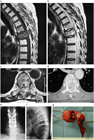

1. がんの既往のある患者が脊椎に痛みを訴えた場合、転移性脊椎腫瘍を念頭に置くことが推奨される(推奨度1)

1. 転移性脊椎腫瘍を疑った場合、全身の造影CTを撮影することが推奨される(推奨度1)

1. 転移性脊椎腫瘍と診断した場合、余命を評価することが推奨される(推奨度1)